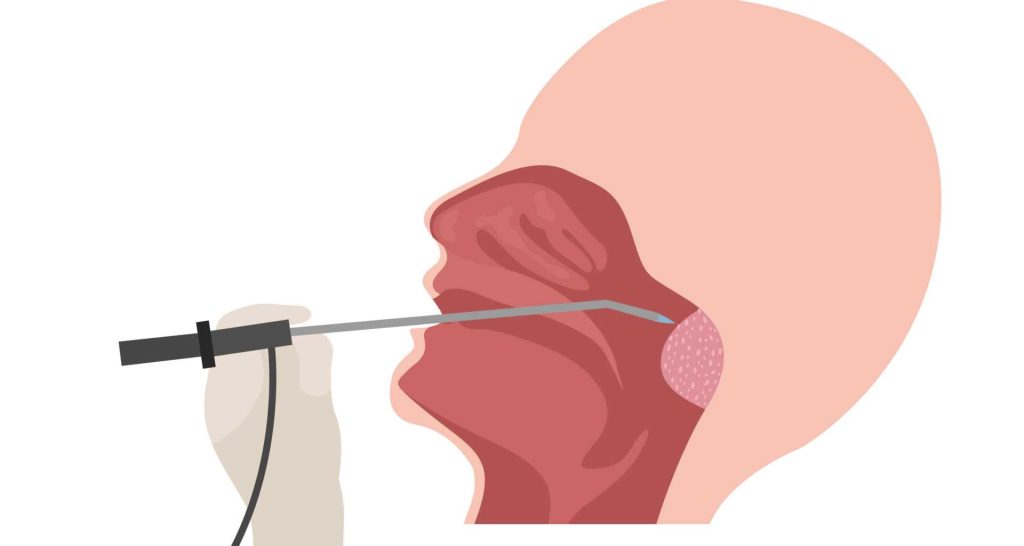

أثناء إجراء جراحة اللحمية الأنفية

تعتمد طريقة إجراء عملية اللحمية الزائدة في الأنف على موقع تلك الأورام في الأنف وحجمها، حيث يزيل الطبيب اللحميات الكبيرة القريبة من مقدمة الأنف عن طريق أداة تمكنه من التقاط لحمية الأنف بسهولة وإزالتها، كما يمتص السوائل الناتجة أيضاً.

قد تحتاج عملية اللحمية إلى غرفة عمليات معقمة وتخدير كلي للمريض، وذلك في حالة إزالة لحميات الأنف الصغيرة والمتعددة، والتي تقع عميقاُ أعلى الأنف في الجيوب الأنفية، وهنا تجرى عملية اللحمية بالمنظار، وهو أنبوب ملحق به كاميرا للتصوير تمكن الطبيب من الرؤية بوضوح لإزالة زوائد الأنف الصغيرة.

تستغرق جراحة اللحمية بالمنظار بضع ساعات قليلة، ويبقى المريض في المستشفى مدة يوم واحد فقط للتعافي.